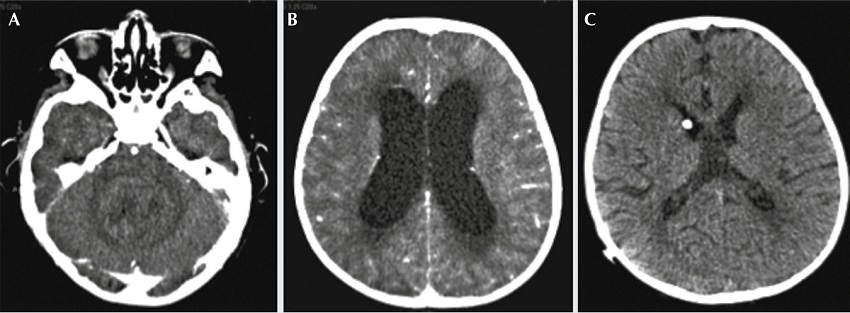

A su ingreso se realizó tomografía axial computarizada donde se observó una tumoración heterogénea que ocupaba y expandía al cuarto ventrículo, con compresión de las estructuras circundantes, y una gran dilatación ventricular con moderado edema transependimario. Dos días después hubo datos de cráneo hipertensivo, por lo que se colocó sistema de derivación ventrículo peritoneal de urgencia (Figuras 1 y 2). Un mes después se realizó craniectomía programada para resección tumoral administrándose 3 dosis de cefalotina como tratamiento antibiótico profiláctico.